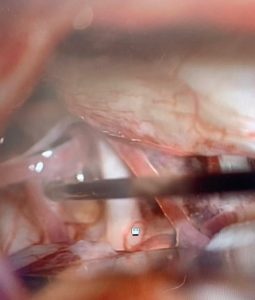

Trigeminal neuralgia microsurgery can be very satisfying for both the patient and the neurosurgeon. I am always humbled and grateful when I see patients who get relief from trigeminal neuralgia, one of the most terrifying and severe forms of facial pain. The pictures below for the final steps in a surgery that I performed for a patient with this debilitating disease. She had lasting relief from her symptoms.

Image 3: The material in place (pointer) that now protects the nerve from arterial pressure.